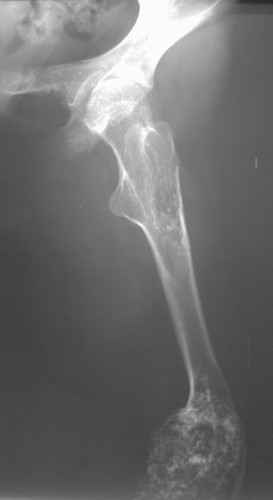

Диагноз: Дисхондроплазия. Варусная деформация дистального метафиза правой бедренной кости; состояние после оперативных вмешательств (1993 и1994 гг.).

Деформация правой нижней конечности с 6 месяцев (стала прогрессировать после года, с момента начала ходьбы). Поставлен диагноз болезнь Олье, варусная деформация, укорочение правой нижней конечности на 4,5 см. 1993 г. - операция остеоклазия на уровне очагов поражения в н/3 правой бедренной кости и в/3 правой большеберцовой кости с одномоментной коррекцией деформации и фиксацией костных фрагментов спицами Киршнера.После начала статической нагрузки (1994 г.) появился рецидив деформации и укорочения. Вторая операция - ЧКО АВФ, аппарат демонтирован через 2недели в связи с развившимся на уровне стержня переломом, после чего находилась в гипсовой повязке до консолидации костных фрагментов. Далеелечилась консервативно в гипсовой повязке. Выраженная деформация и укорочение правой нижней конечности. Относительная длина бедер: справа -34 см, слева - 51 см; анатомическая длина голеней: справа - 29 см, слева - 39 см. Величина варусной деформации на уровне дистального отдела правого бедра составляет - 80 град. Амплитуда движений в коленных суставах (разгибание/сгибание ): справа - 0/0/100 град.; слева - 0/0/30 град. Отмечается боковая и ротационная нестабильность на уровне правого коленного сустава. Амплитуда движений в голеностопных суставах - в норме. Тактика лечения? Заранее благодарю! С уважением,А.В.Владзимирский